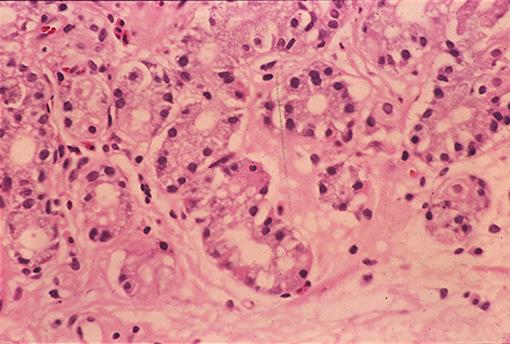

A case of ectopic gastric mucosa which developed in the rectum.

Tumor-like lesions/ectopic mucosa

Large intestine(Colon)/Rectum

Histology

10 - 14